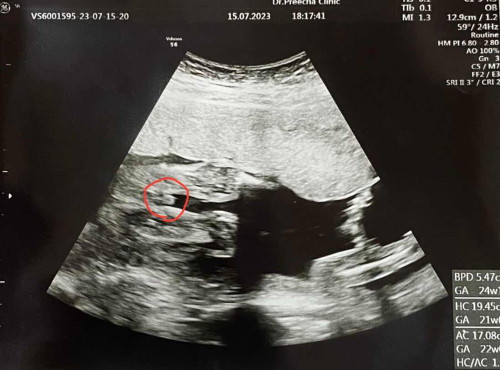

ตัวเเม่เอง ท้องเเรกได้ผู้หญิง ตอนนี้น้องอายุ2ขวบ11เดือน เด็กผู้หญิง น่ารัก ขี้อ้อนมากๆๆ ปากดีมากๆทำให้ทุกคนในบ้านหลงกันหัวปักหัวปรำ พอมาตอนนี้ท้องที่สอง อัลตราซาวน์ได้ผู้ชาย อายุครรภ์ 5เดือนกว่า ตอนท้องที่สองเเม่ก็ลุ้น อยากได้ผู้ชาย พอได้เเล้วรู้สึกตื่นเต้นมาก ตื่นเต้นที่จะได้มีลูกชาย จะได้เลือกซื้อเสื้อผ้าลูกชาย รอคอยน้องออกมา อยากเห็นหน้าเเย่เเล้วค่ะ เเม่เล่าให้ฟังหน่อยค่ะ ตื่นเต้นกันไหมคะท้องที่สอง ปล.กำหนดคลอดเเม่ 14 พย.2566

ตื่นเต้นมากเพราะรอคอยมา 8ปี กว่าจะมีลูก ได้ลูกชายค่ะตอนนี้2ขวบแล้ว ตอนนี้กำลังท้องได้6เดือน ช่วงยังไม่รู้เพศก็แอบหวังขอให้เป็นผู้หญิงเถอะ จนช่วง3เดือนเกิดภาวะแท้งคุกคามเลยไปหาหมอโรงพยาบาลตามสิทธิ์ประกันสังคมหมอได้ซาวน์ดูเด็กให้หมอถามว่าหมอที่รับฝากครรภ์บอกหรือยังว่าเพศไหน แต่หมอเห็นเป็นผู้ชายนะ เราก็ผิดหวังแหละ แต่ไม่เป็นไร คิดว่าหมอคงดูไม่ชัดหรอก แต่ลองให้หมอฝากครรภ์ดูอีกที พอถึงวันนัดเราก็บอกหมอว่าเกิดภาวะแท้งคุกคามค่ะ หมอก็แนะนำให้ตรวจ NIPT ดูเพราะเราอายุ35 แล้ว พอผลออกทางคลินิกก็โทรมาบอกผลปกติดี คุณแม่ได้ลูกชายนะคะ พอได้ยินก็ผิดหวังหน่อย เพราะแฟนอยากได้ลูกสาว เราอยากซื้อชุดกระโปรงให้ลูกใส่ ได้ลูกชายก็ไม่ได้แย่หรอกค่ะ มีของใช้เสื้อผ้าลูกคนแรกพร้อมหมดแล้ว เชฟเงินในกระเป๋ามากอยู่ค่ะ ลูกคนแรกใครๆก็บอกว่า หน้าหวานเหมือนลูกสาวเลย ตั้งใจ 2คนพอแล้วจะปิดอู่ตอนนี้ก็เลยลังเลว่า จะทำหมันดีไหมหรือไม่ทำ กำลังคลอด 11 พย. 2566 แต่คิดไว้หมอน่าจะนัดผ่าคลอดช่วงปลายสิ้นเดือน ตุลา